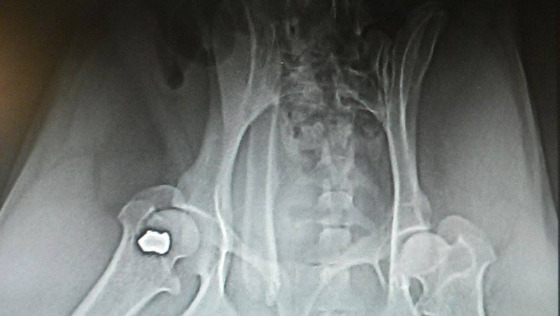

Po konsultacji z lekarzem prowadzącym Michasia zdecydowaliśmy, że podejmiemy próbę leczenia przy użyciu komórek macierzystych. Lekarze użyją ich do ostrzyknięcia pęcherza moczowego. Jest szansa, iż komórki pomogą psiakowi w samodzielnym oddawaniu moczu. Zamówiliśmy je z Warszawy i będą na czwartek rano. Wtedy lekarze wykonają dwa zabiegi ( usunięcie wodonercza i ostrzyknięcie pęcherza) wykorzystując jedno znieczulenie dla dobra Michasia.